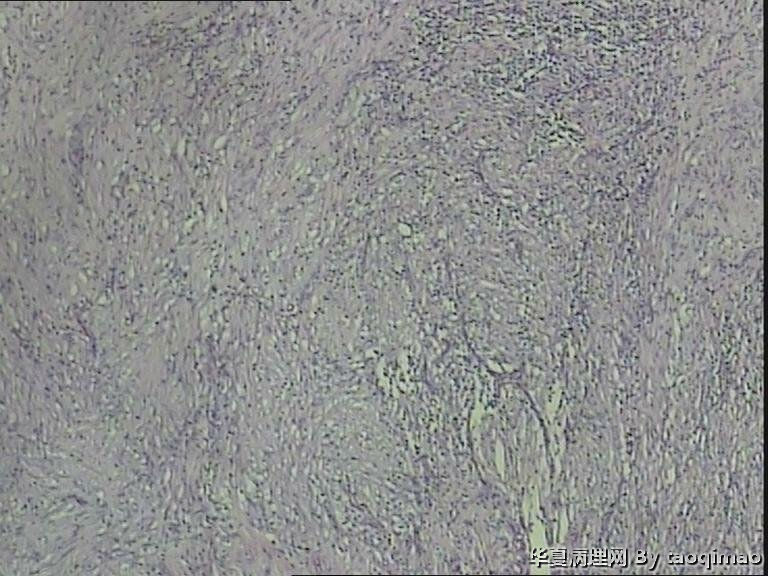

• 胃溃疡?图1

补取的组织

79岁女,胃溃疡,切除胃大部分,与脾有粘连,胃小弯侧可见一溃疡3x2.5x2cm,并且局部胃粘膜增厚,呈皮革胃样外观,切面灰白似粘液样。

巨大溃疡临床诊断,可是看了间质很浆糊,希望老师们给指点些

胃溃疡,黏液变,没看到明确的上皮样细胞